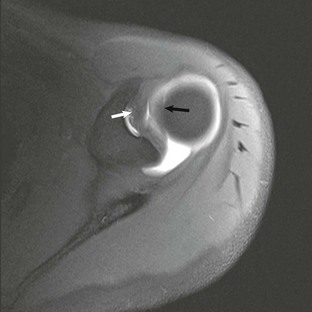

The “hourglass” biceps tendon describes a condition featuring marked tendinosis and hypertrophy isolated to the intraarticular portion of the long bicipital tendon, which prevents the tendon from sliding into the bicipital groove during elevation of the arm.131 Entrapment of the long bicipital tendon causes a mechanical block and pain. This condition occurs most often in association with a full-thickness tear of the rotator cuff, although entrapment occurring in association with partial-thickness rotator cuff tears has been described in case reports as well. Patients present with anterior arm pain and loss of passive elevation of the arm averaging about 10 to 20 degrees. The condition is treated with resection of the abnormal segment and tenodesis of the biceps tendon followed by appropriate treatment of any concomitant injury of the rotator cuff. MRI will show marked tendinosis and thickening limited to the intraarticular portion of the biceps tendon (Fig. 44-33) and is often associated with either a partial- or full-thickness rotator cuff tear.